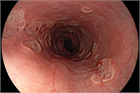

1. クローン病とは、原因不明の、口腔内から肛門周囲までの腸管のどの部位にでも発症する炎症性腸疾患の1つである。